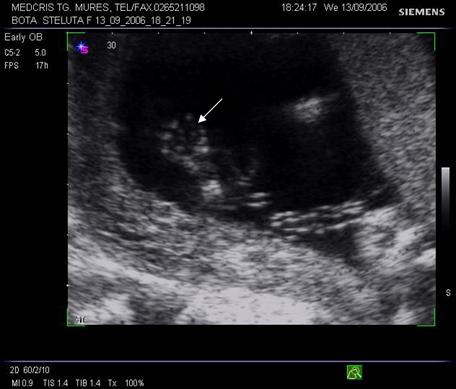

Fig nr. 8. Sarcina 5 sapt la ecografia transvaginala :sac ovular cu vezicula vitelina evidenta marcata cu sageata, retrouterin ovar chistic